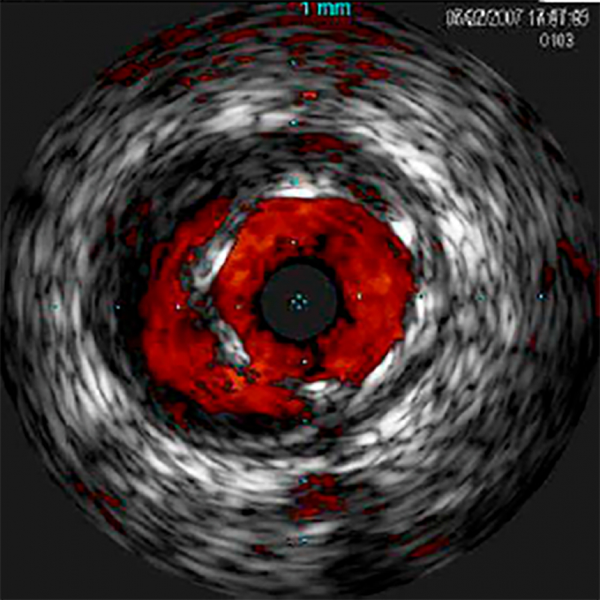

Специализированный режим ультразвуковой визуализации, предназначенный для детекции и оценки перфузии в режиме реального времени во время внутрисосудистых ультразвуковых исследований (ВСУЗИ). Технология основана на анализе движения частиц, что позволяет с высокой чувствительностью отображать микроциркуляцию и отличать перфузию от окружающих тканей.

Режим визуализации ChromaFlo доступен в интегрированной системе Philips Volcano Core, системах Core Mobile, s5 и s5i. С помощью этой функции можно легко оценивать прилегание стента к сосудистой стенке, размер просвета и другие параметры. С помощью функции ChromaFlo нажатием кнопки можно выделить кровоток красным цветом.

Функцию ChromaFlo можно применять для исследований периферических и коронарных сосудов, включая исследования основного ствола левой коронарной артерии, бифуркации, поверхностной бедренной и подвздошной артерий. Эта функция создана для быстрой оценки размера просвета сосуда и прилегания стента к сосудистой стенке; она облегчает определение таких объектов, как ветви сосудов, разрывы сосуда и тромбы, а также облегчает оценку распределения бляшек в области бифуркаций. Функция ChromaFlo совместима с предназначенными для системы Philips Volcano цифровыми катетерами для ВСУЗИ Eagle Eye Platinum, работающими по технологии «plug-and-play».

Функция ChromaFlo выделяет кровоток красным цветом, облегчая определение следующих объектов:

Размер просвета сосуда

Прилегание стента к сосудистой стенке

Ориентация бляшки в области бифуркаций

Разрывы

Тромбы